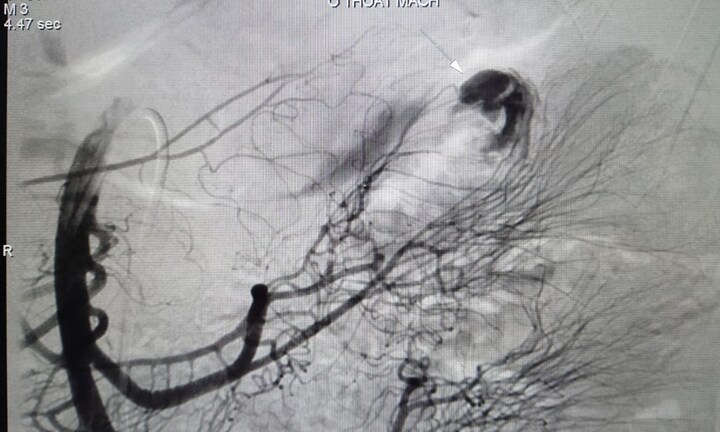

Bác sĩ CKII Cao Việt Dũng - Giám đốc chuyên môn Bệnh viện Đa khoa Sài Gòn Nha Trang cho biết, đơn vị này vừa phẫu thuật thành công cho cụ ông N.T.T. (92 tuổi, TP.Nha Trang) bị thủng ổ loét dạ dày nặng có tiền sử loét dạ dày mạn tính do điều trị không đủ liều, theo báo Khánh Hòa.

Khi tiếp nhận người bệnh, xác định đây là ca nặng, kíp trực cấp cứu đã ngay lập tức hội chẩn với bác sĩ ngoại tiêu hóa. Sau thăm khám và có kết quả cận lâm sàng, ekip bác sĩ xác định bệnh nhân thủng dạ dày nặng và nhanh chóng tiến hành phẫu thuật cấp cứu. Sau phẫu thuật, sức khỏe người bệnh ổn định, đang được chăm sóc theo dõi tại khoa Ngoại của bệnh viện.

“Trường hợp ông T., với vết thủng có đường kính 1cm trên nền ổ loét xơ chai nặng, ổ bụng có nhiều dịch tiêu hoá và màng viêm màu trắng đục, cho thấy đây là vết thủng lâu ngày do loét dạ dày mạn tính. Nếu gia đình đưa đến bệnh viện chậm thì sẽ rất nguy hiểm đến tính mạng người bệnh”, bác sĩ Dũng cho hay.